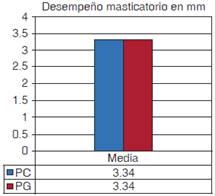

Se contó con la participación inicial de 30 sujetos, sin embargo, se redujo a seis, principalmente por motivos de salud (caídas, enfermedades físicamente limitativas, fallecimiento, entre otros). El peso de las prótesis aumentó hasta en un 40% (z -2.201 p = 0.028). La prueba de estabilidad reveló que las PG fueron más estables (p = 0.046). En cuanto al DM con el TMP, no se encontraron diferencias entre las prótesis (valor z -.125, p = 0.893).

El profesional le indica generalmente al paciente portador de prótesis total que los alimentos deben estar bien hidratados para facilitar el rompimiento de los mismos; el alimento artificial Optocal al ser plástico, dificulta la entrada de saliva disminuyendo su humectación, por tanto, se podría modificar para apegarse más al alimento natural consumido por estos pacientes, sobre todo porque se ha demostrado el detrimento de dicho DM en portadores de prótesis totales y más en rebordes atróficos14 comprometiendo la satisfacción del tratamiento protésico. Sin embargo, la estandarización del material nos facilita la obtención de resultados más objetivos. Ciertamente, varios factores intervienen en la determinación de una buena masticación, como son la edad, la salivación, el tamaño del reborde residual, la dimensión vertical disminuida o aumentada, la retención de las dentaduras, la disposición de los dientes artificiales incluyendo la amplitud de caras oclusales, hasta la calidad y dureza de los alimentos. En este estudio se presentaron dificultades con la prueba de DM a pesar de que el alimento prueba tiene una dureza 40% menor al alimento usado en pacientes dentados. Al comparar el TMP de los pacientes de esta investigación (3.34 mm) con el promedio de hombres y mujeres jóvenes con dentición completa sin maloclusión medida con Optosil (1.8 mm) presentan un DM 46% menor pero considerando que el Optosil es mucho más duro que el Optocal la desventaja es aún mayor.30 El no haber encontrado diferencia en TMP a pesar de que los pacientes referían poder comer mejor con las PG se debe a que el efecto es pequeño, por lo que el tamaño de la muestra debería ser mucho mayor. En otros estudios6 llama la atención que el TMP sólo disminuye un 9% entre las prótesis originales y la nueva, implicando que el beneficio de la capacidad de fractura del alimento se incrementa poco. Estos datos confirman que los pacientes desdentados que requieren dentaduras totales están muy afectados en su función masticatoria, teniendo como problema el masticar alimentos duros.31-34 Se sabe que los pacientes con problemas para masticar debido al edentulismo parcial o total, presentan deficiencias nutricionales35-37 y alteraciones sistémicas, como la dispepsia,5 incrementando la ingesta de alimentos blandos y carbohidratos, disminuyendo los alimentos ricos en fibra37,38 y las proteínas que hay en la carne animal.34-35 Estos problemas disminuyen la calidad de vida e incrementan la mortalidad (Heath, 1972, Miura, 2000, de Souza-e-Silva, et al 2010, Greksa, 1995 y Sherder, 2008), por lo que es importante mejorar la función masticatoria.